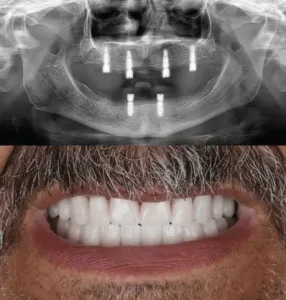

Usually, full mouth dental implant treatments use four, six or eight implants per single jaw. The increased number of implant screws provides more stability to the attached fixed bridge that replaces the patient’s teeth, though some patients can lack jawbone density for eight or six implants per jaw.

The process starts with a full dental consultation, during which dentists check the patient's oral health and talk about their specific wants and goals. Diagnostic imaging, such as panoramic X-rays, may be used at this first visit to check the health of the jawbone and structures nearby. With this information, the dentist can make a personalised treatment plan for you, discussing options such as implant systems and any necessary dental preparation.

Stage 2: Fixing implants

The next stage after creating the treatment plan is to surgically place the implants. Dental doctors insert titanium screws into the jawbone using tiny incisions. For the patient's comfort, we apply anaesthesia during this process. The screws hold the new teeth in place. Once the implants are in, the bone needs to heal for a few months so that it can join with the implants, making the tooth stable and strong.

Stage 3: Attachment of permanent teeth

Total implants required for complete mouth restoration